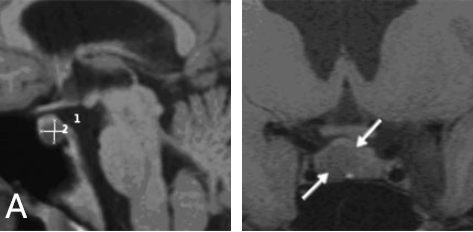

核磁共振成像顯示垂體窩中有一個(gè)小腫瘤,將正常垂體向左側(cè)移位

核磁共振成像顯示垂體窩中有一個(gè)小腫瘤,將正常垂體向左側(cè)移位。

INC國(guó)際神經(jīng)外科醫(yī)生集團(tuán)旗下組織世界神經(jīng)外科顧問團(tuán)(WANG)成員、世界神經(jīng)外科學(xué)會(huì)聯(lián)合會(huì)(WFNS)內(nèi)鏡委員會(huì)前主席Henry W.S. Schroeder(施羅德)教授決定采用內(nèi)鏡經(jīng)鼻手術(shù),成功切除了腫瘤。術(shù)后一年的核磁共振成像顯示,泌乳素瘤已完全切除,垂體功能正常。內(nèi)分泌檢查顯示泌乳素水平恢復(fù)正常,其余激素的表現(xiàn)也十分正常,青春之花重新綻放!

術(shù)后核磁共振成像顯示腫瘤已完全切除。泌乳素水平趨于正常。垂體正常工作,無需補(bǔ)充激素。